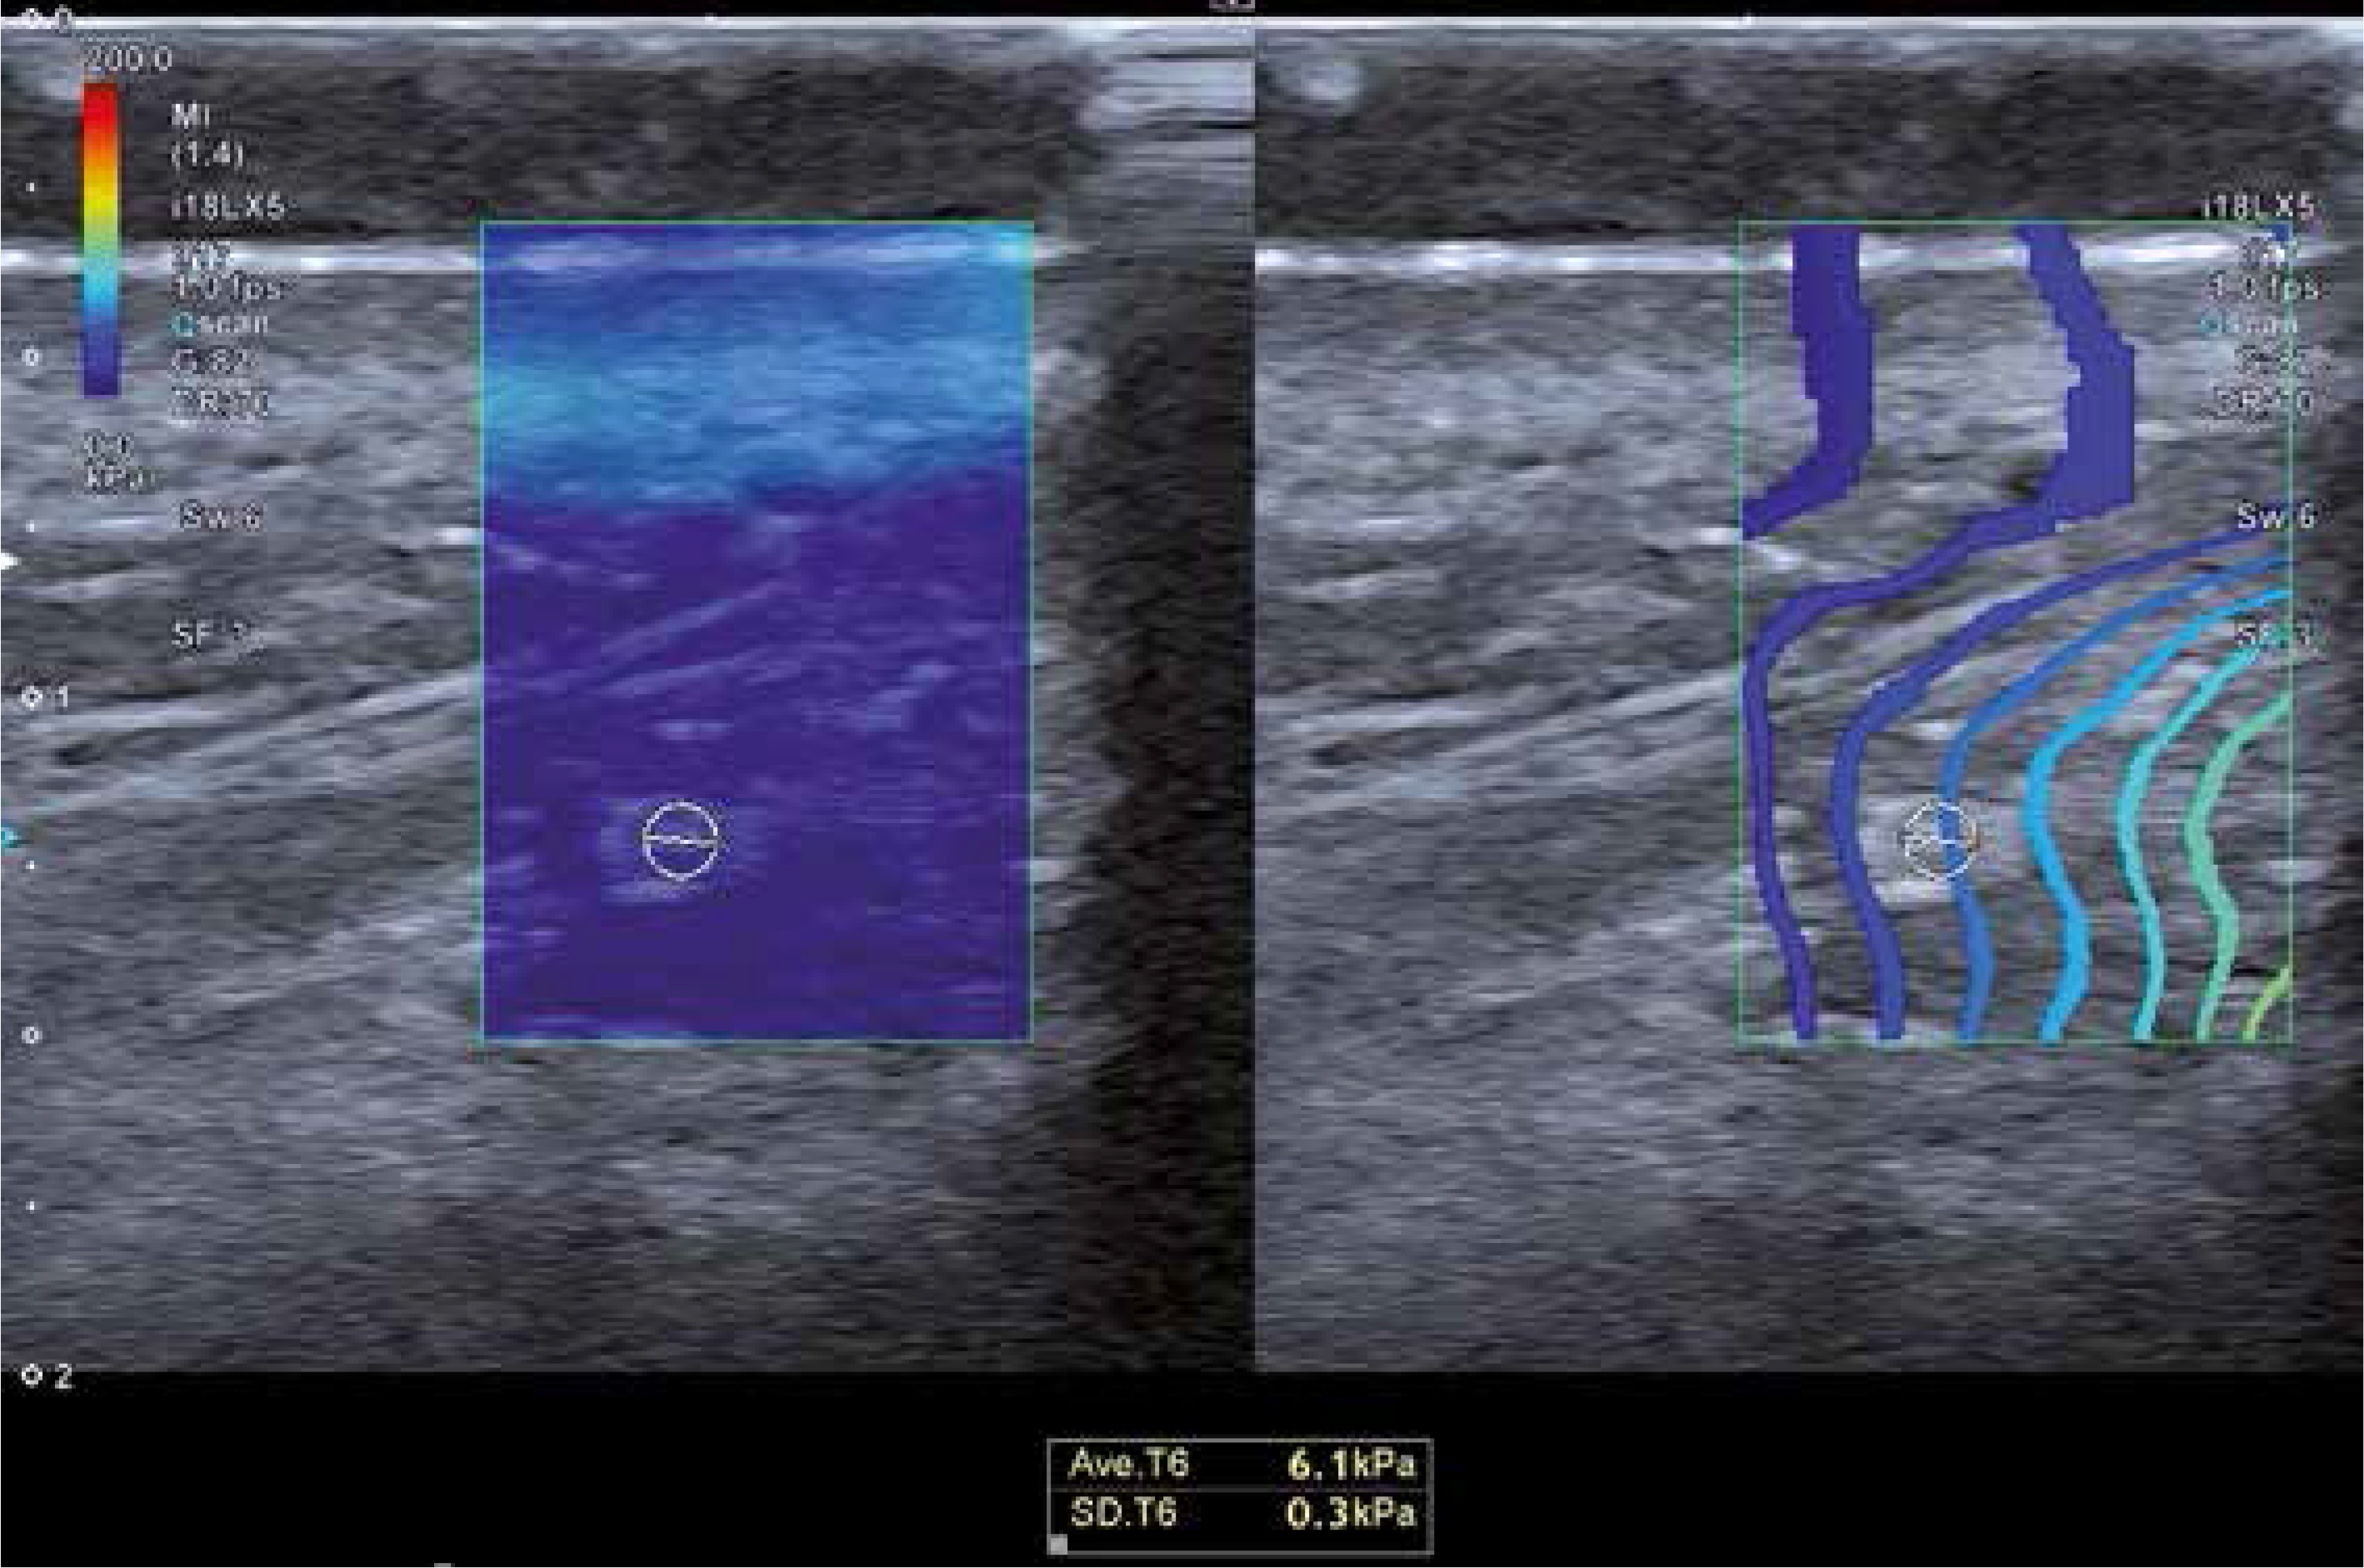

Prior to the laser treatment, all participants were subjected to ultrasonographic examination and elastography of the DMCFC. The examination was carried out with the patient in a supine position. Sonographic scans were obtained with a Toshiba iAplio 900 ultrasonograph with a 5–18 MHz transducer (Canon Medical Systems, Nasushiobara, Japan). During the examination, the face was covered with a hydrogel pad and a thick layer of gel. The transducer was placed perpendicularly to the skin, and transverse scans were obtained. Upon visualization of the area of interest, the thickness of the DMCFC in millimeters was measured. Then, SWE was performed, after stabilizing the elastographic image. The region of interest (ROI) was placed in the center of the screen, to cover approximately 80% of the examined structure. Three measurements were taken for each ROI and the average result was recorded. The reference value for the elasticity modulus was set at 100 kPa. Representative elastographic images are presented in Figure 2.